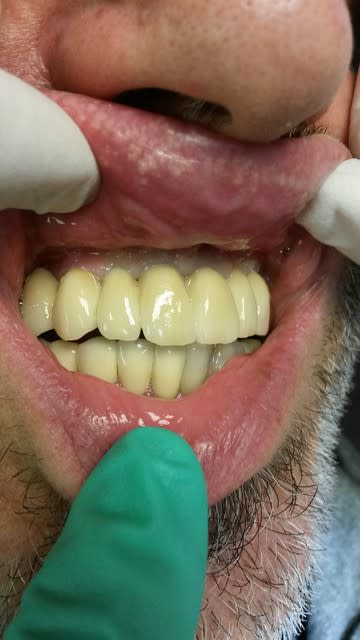

Allez, posé y'a 15 minutes. Collage multilink.

Img 2978 tqx1pw - Eugenol

Img 2984 bxc0kj - Eugenol

Img 2973 ewwctg - Eugenol

Belles préparations , attention par contre à ne pas trop " creuser" le congé (voir 22), ce qui entraîne une limite un peu pointue et fragilise la céramique.

-preps un peu agressives, j'étais du même avis en voyant le modèle, c'est pour ça que je les ai postées: comme ça c'est confirmé. Je vais avoir la main un peu plus légère sur les prochaines.

-par contre pour le congé 22 23 un peu creusé, d'anciennes CCM étaient présentes, je pense donc que c'était déjà le cas sur les preps antérieures.

-A noter, ça se voit mal sur les photos, que 11 12 13 sont des couronnes 3/4, la limite palatine se situe 3mm au-dessus de la gencive.

-Et photo sourire le jour de l'essayage, donc avant retouche de la 22. Bon, l'anesthésie ne facilite pas un sourire naturel ;-)